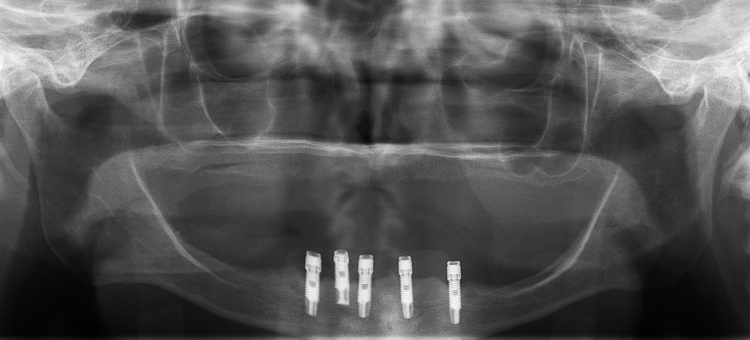

Fig. 1: Pre-treatment radiograph showing five implants clustered in the anterior mandible.

A 73-year-old woman with a history of 11 years of complete edentulism of the maxilla and mandible, and five endosseous implants in the anterior mandible, presented with a chief complaint of a non-retentive and unstable lower denture. The implants were standard diameter, externally hexed, Brånemark fixtures. She had moderate resorption of both the maxillary and mandibular residual ridges (Fig. 1).

The patient had bone loss involving the implant bodies but comparing the radiographic evidence available, documenting her condition through the years, it appears the bone loss occurred soon after implant placement and no appreciable change was seen thereafter.